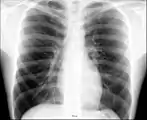

При изучении рентгеноанатомии органов грудной клетки обращают внимание на рентгеновскую структуру видимых костей и мягких тканей грудной клетки; форму и прозрачность для рентгеновских лучей областей, на которые проецируется лёгочная ткань (так называемых «лёгочных полей»), а также их структуру, сформированную тенями сосудов лёгких («лёгочный рисунок»); расположение и структурность корней лёгких; положение, форму куполов диафрагмы и синусов плевральных полостей; форму и размеры тени средостения (в том числе сердца).

Рёбра являются ориентиром для оценки расположения других структур грудной клетки. При обзорной рентгенографии лёгких в прямой проекции в норме визуализируются передние отрезки верхних пяти или шести пар рёбер. Рёберный хрящ на рентгенограмме не виден (при отсутствии его обызвествления), в связи с чем изображение грудинных концов рёбер прерывается на некотором расстоянии от грудины. Тени передних отрезков рёбер направляются кнаружи и кверху от срединной линии; задних отрезков — кнаружи и книзу. Помимо изображения рёбер, на рентгенограммах грудной клетки визуализируются тени ключиц и лопаток (последние при правильно выполненном снимке не накладываются на лёгочные поля). На рентгенограмме, выполненной с оптимальными условиями, также различимы тела первых трёх грудных позвонков. Среди теней мягких тканей, покрывающих грудную клетку, различимы изображения грудино-ключично-сосцевидных мышц (в проекции медиальных отделов верхушек лёгких); грудных мышц (в верхне-латеральных отделах лёгочных полей); молочных желез и сосков. Иногда над ключицами можно увидеть тонкие тени кожных складок.[3][4]

Лёгкие на рентгенограмме образуют лёгочные поля, располагающиеся по обе стороны от интенсивной тени средостения. Правое лёгочное поле короче и шире левого. В лёгочных полях различают верхушки (зоны выше ключиц), верхние отделы — от верхушек до передних отрезков вторых рёбер, средние отделы — между вторыми и четвёртыми парами рёбер, и нижние отделы — от четвёртых рёбер до диафрагмы. Лёгочные поля в норме очень светлые (тёмные на негативе) из-за высокой рентгенопроницаемости заполненной воздухом лёгочной ткани. Структура лёгочных полей называется лёгочным рисунком, анатомическим субстратом которого являются лёгочные сосуды и, в малой степени, лёгочный интерстиций. Лёгочный рисунок визуализируется в виде переплетения сосудистых теней тяжистого, округлого и овального вида, более интенсивных в местах их пересечений. В направлении от корней лёгких к периферии рисунок лёгочных сосудов становится беднее и совсем не визуализируется на расстоянии 1—1,5 см от края лёгочных полей. Лёгочный рисунок наиболее густой в нижних отделах лёгочных полей, обедняясь к верхушкам. Тени бронхов на рентгенограмме визуализируется в виде двойных полосок или колец с просветлением внутри.[3][4]

Тень корней лёгких определяется парамедиастинально на уровне передних отрезков II—IV рёбер, левый корень располагается несколько выше правого и частично скрыт тенью средостения. Ведущим анатомическим субстратом в формировании тени корней лёгких являются лёгочные артерии и бронхи, в меньшей степени — лёгочные вены и другие структуры. В норме корни лёгких имеют неоднородное изображение, представляя собой структурированную совокупность элементов различной плотности. В корнях лёгких различают головку, тело и хвост. Правый корень визуализируется на всём протяжении в виде лентовидной, суживающейся книзу изогнутой тени средней интенсивности, отделённой от тени сердца промежуточным и нижнедолевым бронхами. К периферии от корней лёгких отходят лёгочные сосуды, причём артериальные ветви имеют более вертикальное направление, венозные — более горизонтальное. Ширина корня лёгкого соответствует ширине его основного артериального ствола; в норме она равна ширине бронха, отделяющего корень от средостения, и не превышает 1,5 см.[3][4]

Нижние границы лёгочных полей образованы тенью диафрагмы. Куполы диафрагмы имеют вид изогнутых кверху дуг, направляющейся от боковых отделов грудной стенки к средостению. Правый купол диафрагмы при глубоком вдохе располагается на уровне передних отрезков V—VI рёбер, левый — на одно ребро ниже. В боковых отделах куполы диафрагмы образуют острые углы с рёбрами, формируя рёберно-диафрагмальные синусы. В медиальных отделах куполы диафрагмы, пересекаясь с тенью средостения, формируют менее глубокие кардио-диафрагмальные синусы, форма которых варьирует. Правый купол диафрагмы снизу не дифференцируется от тени печени, под левым куполом диафрагмы обычно видны единичные просветления, соответствующие скоплениям газа в желудке и селезёночном углу ободочной кишки.[3][4]

Сердечно-сосудистая тень занимает центральное положение на рентгенограмме органов грудной клетки. На рентгенограмме в прямой проекции её контуры в норме формируют две дуги справа и четыре — слева. Нижняя дуга правого контура образована правым предсердием, верхняя, более медиальная — восходящей частью аорты и верхней полой веной. Первая (верхняя) левая дуга образована дугой и начальным отделом нисходящей аорты, вторая — лёгочным стволом, третья — ушком левого предсердия, четвёртая — левым желудочком. В области второй и третьей дуг контур тени средостения вогнут и носит на этом уровне название «талия сердца»; эта зона является границей между сердцем и связанными с ним сосудами.[5]